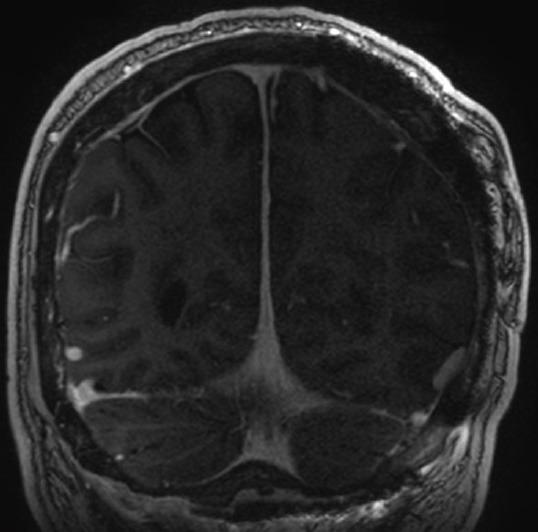

A 48-year-old male presented after 3 days of worsening headaches and blurry vision. Preoperative imaging demonstrated an 11 × 5-cm extra-axial mass that avidly enhanced with gadolinium in the region of the torcula. Angiography demonstrated occlusion of the involved portions of the superior sagittal sinus, torcula, and proximal left transverse sinus. Cortical drainage occurred via the veins of Labbι and deep drainage via an occipital sinus. Using image-guided stereotaxy, a wide-excision scalp resection and craniectomy with sinus exploration was planned for complete tumor removal. Parasitized cortical veins were preserved. Occluded portions of the superior sagittal sinus and left transverse sinus were resected along with the invaded parts of the falx and tentorium. The walls of the straight sinus, torcula, and right transverse sinus were repaired primarily to facilitate deep drainage. A latissimus dorsi free flap was used to reconstruct the scalp defect. Routine follow-up magnetic resonance imaging (MRI) at 18 months demonstrated no evidence of recurrence or regrowth.

一名48岁男性在头痛和视力模糊加重3天后就诊。术前影像学检查显示一个11×5厘米的轴外肿块,在窦汇区域钆增强明显。血管造影显示上矢状窦、窦汇和左侧横窦近端受累部分闭塞。皮质引流通过Labbe静脉进行,深部引流通过枕窦进行。采用影像引导立体定向技术,计划进行广泛的头皮切除和颅骨切除术并探查窦,以完整切除肿瘤。保留寄生的皮质静脉。切除上矢状窦和左侧横窦的闭塞部分以及镰和小脑幕的受累部分。直接修复直窦、窦汇和右侧横窦的壁以促进深部引流。使用背阔肌游离皮瓣修复头皮缺损。18个月的常规随访磁共振成像(MRI)显示无复发或再生长迹象。